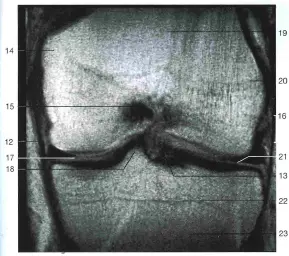

Мениски коленного сустава – этодве плотные полукруглые (серповидной формы) прокладки, которые расположены между мыщелками большеберцовой и бедренной костей. Они обеспечивают полное прилегание суставных поверхностей друг к другу, заполняя боковые полости коленного сустава. Мениски – это уплотнители сустава. Их роль – смягчение давления на хрящ и уплотнение сустава так, что бы сустав был стабильным при движении. Мениск принимает на себя ощутимую часть нагрузки на сустав и стабилизирует его движение.

Мениск на разрезе имеет треугольную форму (рис. 1, МРТ колена: мениски черного цвета под номерами 17 и 21). Наружный утолщенный край крепится к суставной капсуле, спереди и сзади – к кости (область межмыщелкового возвышения). Внутренний край – тонкий, не содержит сосудов, выполняет только функцию уплотнения.